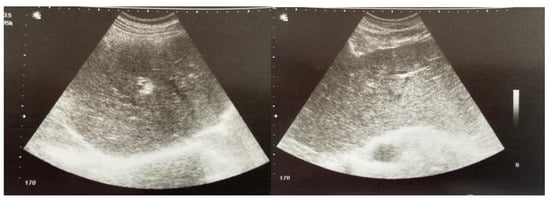

2. Case Presentation